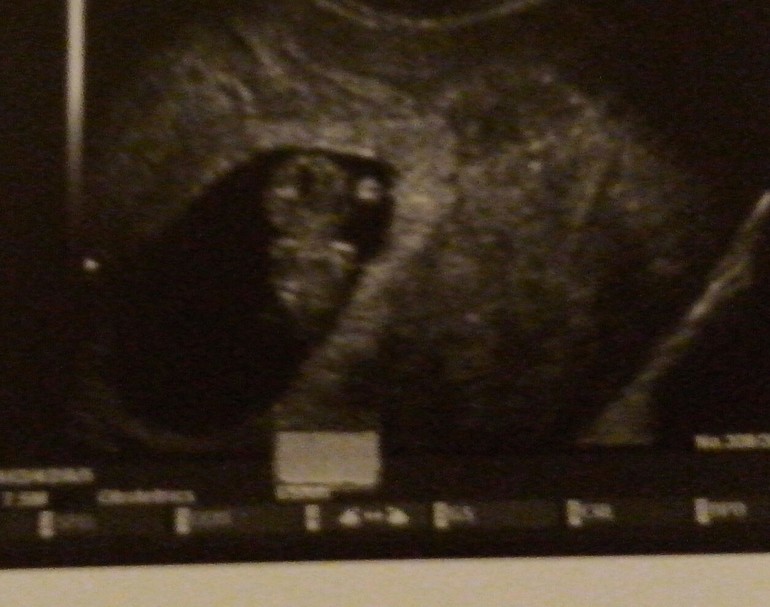

жду девочку, 13 неделя

Приветик мои хорошие.Дела у нас хорошо,вчера встала на учет. Незнаю как по анализам,а самочувствие прекрасное.Токсикоза уже нет.На УЗИ ходила слушала сердечко еще раз уже мой пупсик вырос...лежит попкой)))На фото нам 9 недель....а скоро скрининг на 12 неделе в ожидании))